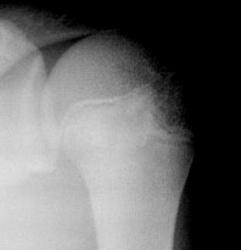

ОК, Петрович! Глубокий вдох, медленный выдох - я спокойна! Ладно Вам, не такая уж я узкая, как Вам хочется думать. Я ж 5 лет рентгенологом работала и по стационару, и по неотложке. А в скоропомощной больнице - это срок, концентрация серъезной патологии очень большая. И, работая на МРТ, неотложку подхватываем. Насчет "атрофировалась" - восприму, как комплимент, значит, все-таки была такая функция! Я сталкивалась недавно с подобной картиной у пациентки с травмой лучезапястного сустава. Линия затемнения шла по бывшей зоне роста. Смотрели, крутили так и эдак (клиника + рентген, никаких 3D реконструкций!). В интересах больной остановились на переломе (на КТ направляла, но она не пошла). Через неделю пришла уже без гипса на контроль. Сняла сама, ничего не болит. R-картина стабильная. В данном случае линия в шейке плеча анатомической, место для перелома нечастое. Так, чтобы полное боковое смещение с захождением по длине - нет. Вколоченный - не думаю. Четкий контур линии, деформации кости нет, внутренний контур головки ровный. А как Вы видите эту ситуацию с учетом "объемного восприятия"? А то опять - покритиковал, пошумел, а свое мнение высказать? Забыл?

Насчет линейной тени (две медиальные стрелки) - думаю, не перелом это, закрытая зона роста.

Однозначно, линия, указанная стрелками, это бывшая ростковая зона.

Мое мнение, что анатомическая шейка плечевой кости абсолютно интактная! Пациент достаточно молод.